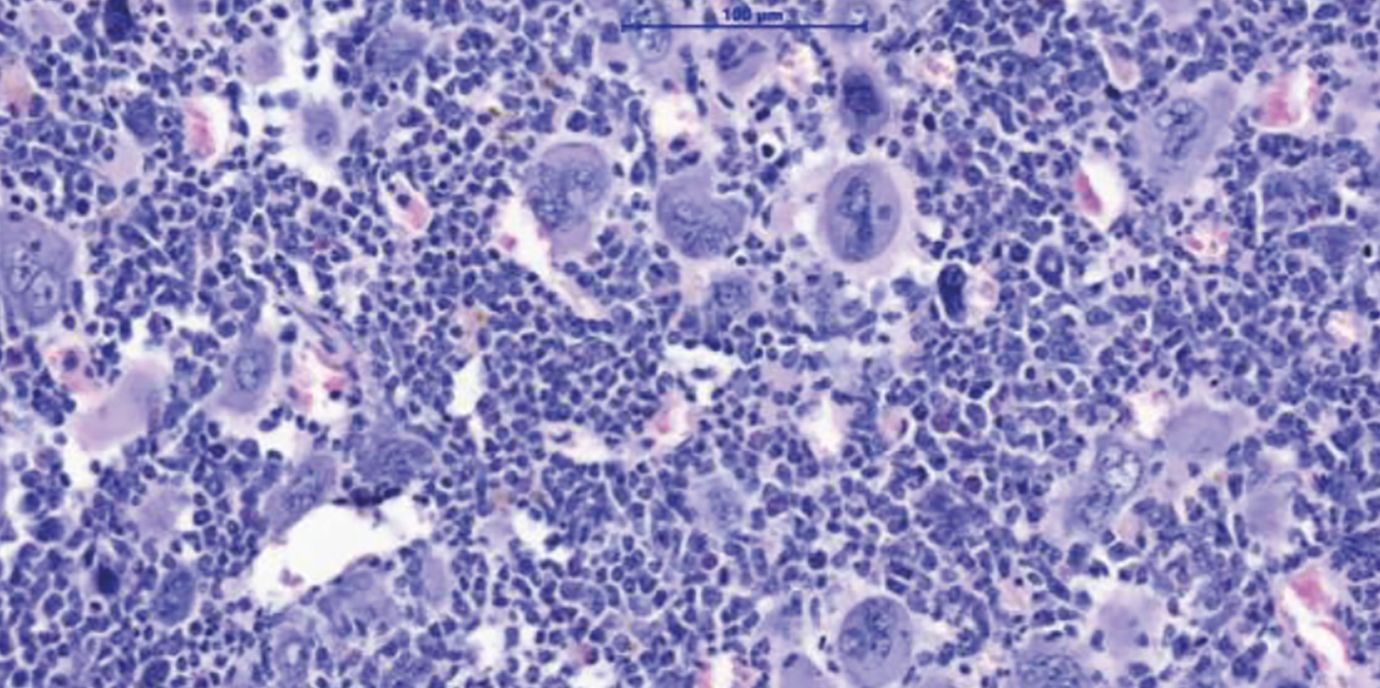

Myeloproliferative Neoplasien (MPN) sind Blutkrebserkrankungen, die durch eine Überproduktion von Blutzellen gekennzeichnet ist. Diese Erkrankungen treten in der Regel ab einem Alter von 60+ Jahren auf und können über lange Zeit gut kontrolliert werden. Gefährlich werden MPN vor allem nach dem Übergang in eine Myelofibrose – eine lebensbedrohliche Vernarbung des Knochenmarks. Eine allogene Stammzelltransplantation bietet für die betroffenen Patient:innen bis heute die einzige Aussicht auf Heilung. „Wir brauchen dringend neue Therapiekonzepte. Eine Stammzell-Transplantation ist für viele Patient:innen aufgrund ihres hohen Alters oder wegen Begleiterkrankungen mit zu hohen Risiken verbunden“, erklärt Dominik Wolf, Direktor der Univ.-Klinik für Innere Medizin V (Hämatologie und Onkologie) an der Medizinischen Universität Innsbruck, den Hintergrund einer soeben im Fachjournal Nature Communications hochrangig publizierten Forschungsarbeit, die er konzipiert und gemeinsam mit Lino Teichman und Miriam Körber vom UKBonn durchgeführt hat. „Wir zeigen in dieser Arbeit ein mögliches neues Therapiekonzept auf, das man klinisch weiterentwickeln sollte“, sagt Wolf, der gemeinsam mit Lino Teichmann als Letzt- und korrespondierender Autor firmiert. Den Wissenschafter:innen ist es gelungen, das NLRP3-Inflammason im Tiermodell zu hemmen und dadurch deutliche Verbesserungen des Krankheitsverlaufs zu erzielen: Die Knochenmarksvernarbung und die Milzvergrößerung bildeten sich zurück und das Blutbild verbesserte sich.

„Wir haben uns erstmalig damit beschäftigt, welche funktionelle Rolle das NLRP3-Inflammasom für die Entzündungsreaktion bei myeloproliferativen Neoplasien hat“, sagt Erstautorin Ruth-Miriam Körber vom Universitätsklinikum Bonn. Dafür haben die Mediziner:innen in Zusammenarbeit mit der German Study Group of MPN (GSG-MPN) eine große Anzahl von Proben ausgewertet und die Entzündungsreaktionen kartiert, bevor sie anhand unterschiedlicher Techniken die Aktivierung des NLRP3-Inflammasoms bei den Patient:innen und auch im MPN-Tiermodell nachweisen konnten.

„Wir haben eng mit Eicke Latz, dem Leiter des Deutschen Rheuma-Forschungszentrums in Berlin, kooperiert, der uns verschiedenste Tools zur Verfügung gestellt hat. Damit konnten wir zeigen, dass diese Entzündungsfaktoren wirklich in Abhängigkeit von NLRP3 produziert werden. Besonders interessant war, dass wir das NLRP3 genetisch in Knockout-Mäusen und auch mithilfe eines neuartigen und spezifischen NLRP3-inhibierenden Medikaments hemmen konnten“, spricht Wolf einen möglichen Therapieansatz an. Dank IFM-2384, einer Substanz, die ebenfalls von Eicke Latz bereitgestellt wurde, konnte im Tiermodell eine deutliche Verbesserung erzielt werden. „Die Knochenmarksvernarbungen und auch die meistens sehr ausgeprägten Milzvergrößerungen gingen zurück. Wir konnten auch das Blutbild verbessern“, zählt Wolf auf.

In einer tiefergehenden Analyse sahen die Forscher:innen, dass vor allem die Überproduktion der Blutplättchen infolge der NLRP3-Blockade deutlich reduziert wurde. „Das NLRP3-Inflammasom spielt eine große Rolle als Gefahrensensor. Bei akutem Stress – wie